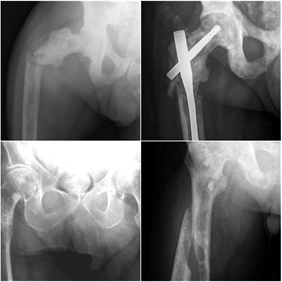

El 80% de las metástasis óseas se relacionan, por orden de frecuencia con el cáncer de mama, pulmón, próstata y riñón. Las metástasis óseas que se localizan en huesos largos suelen localizarse en el fémur, con especial predilección por la zona de la cadera.

El fémur es la localización principal, con predominio de la zona de la cadera. Otras localizaciones son la columna vertebral, la pelvis, los huesos planos y el húmero. En la espalda el dolor suele estar presente antes que los cambios radiográficos, mientras que cuando el dolor se localiza en los huesos largos suelen ya existir lesiones con riesgo de fractura.

En el cáncer diseminado el tratamiento de las metástasis suele ser paliativo, mediante estabilización de la fractura con osteosíntesis o implante de prótesis. En ocasiones la osteosíntesis se suplementa con aporte de cementos biológicos para aumentar la estabilidad o se realiza radioterapia complementaria. En casos de metástasis únicas, el tratamiento quirúrgico radical de la metástasis puede estar indicado, lo que hace necesaria la valoración conjunta de traumatología oncológica y oncología médica ante la detección de una lesión metastásica ósea en nuestra práctica.

Ante la sospecha de una fractura patológica de origen metastático debemos tener un enfoque multidiscilplinar, tanto traumatológico como oncológico, con fin de realizar tanto el tratamiento específico de la fractura como el estadiaje oncológico.